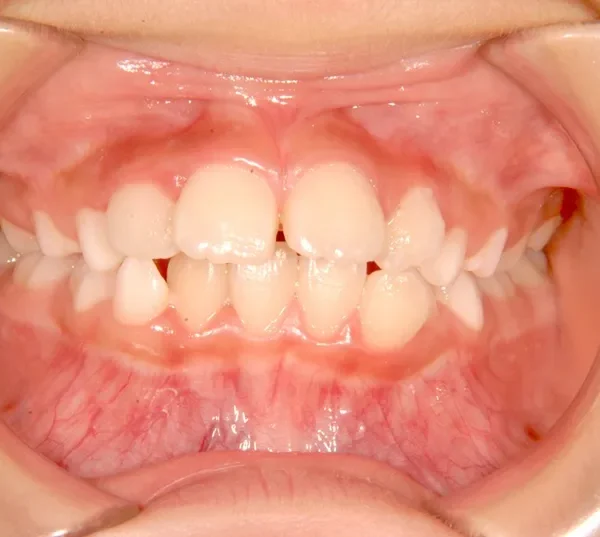

初診時年齢 小学校3年生 (女性) 主訴 出っ歯・前歯がゆがんでいる

診断名 叢生・上顎前突 装置名

状態 永久歯が生える隙間がない(叢生)

ガタガタ・でこぼこに生えている(叢生)

出っ歯(口元が出ている/上顎前突)

出っ歯と前歯のゆがみを主訴に来院されました。

低学年時は取り外しの装置を使用し、高学年になってからは見えにくい固定式の装置を使用して治療しました。

治療回数48回、7年2ヶ月の治療期間で矯正治療を終了しました。

主訴が改善され、ご満足頂きました。